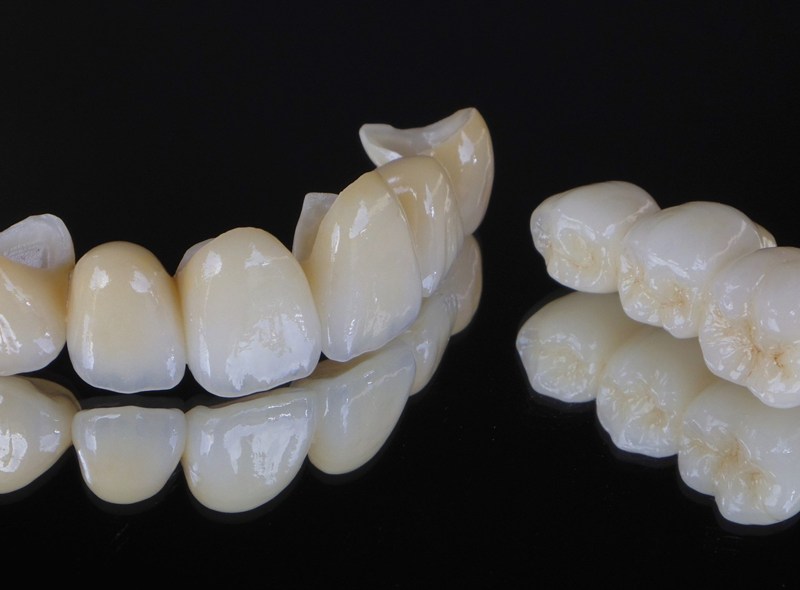

セラミックの被せ物では、自然な歯が持つ透明感や艶といった美しさを、白さはもちろんのこと、限りなく忠実に再現できます。神経を取り除いたことで歯が変色してしまった場合や、ホワイトニングだけでは理想の白さが得られなかった場合でも、セラミックの被せ物を用いることで、本来の美しい歯の色を取り戻すことが可能です。

高強度のセラミック素材です。奥歯のクラウンやブリッジにも適しており、長期間にわたって美しさと機能性を維持できます。金属アレルギーの心配もなく、変色もしにくいのが特徴です。